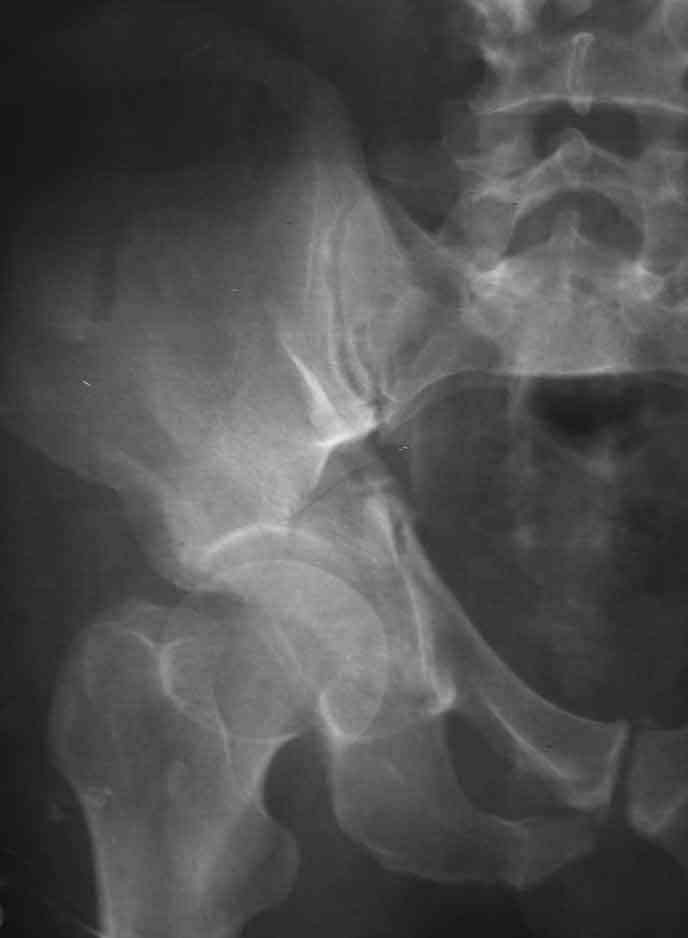

Fr acetabulum

This is a 57 y old male.

Your input is welcome as to the classification of this fratcure, as well as the proposed management.

Unfortunately, CT is not available.